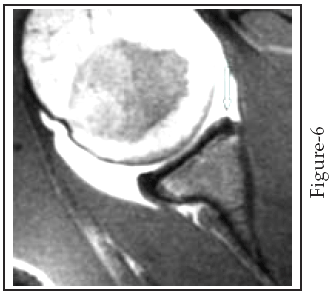

The reason behind the first false-negative case was not full distention of the joint likely due to inconvenience of the patient during joint filling, however in the second false-negative case the report of the absence of the anterior labrum as a normal variant (Buford complex) proved arthroscopicaly as complete detachment of the anterior labrum ( Fig 6) .

Fig-6: An axial T1-weighted MR arthrogram for an 18 year male patient with shoulder instability. The glenoid labrum has a rounded and may be irregular contour (small arrow). This case was reported as Buford complex (normal variant) but it proved to be a Bankart lesion by arthroscopy.